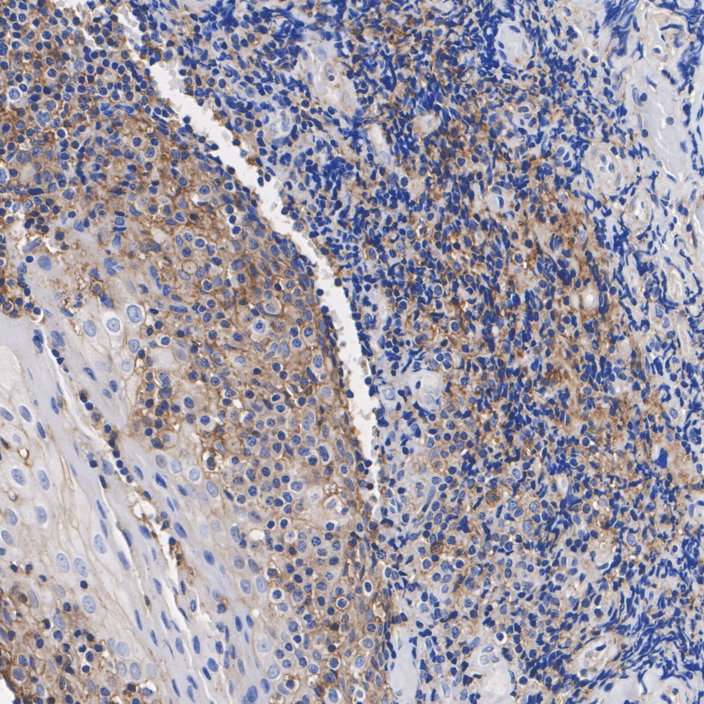

Catalog# ET1701-92

Fas / CD95 Recombinant Rabbit Monoclonal Antibody [JJ0942]

IHC-P

Human